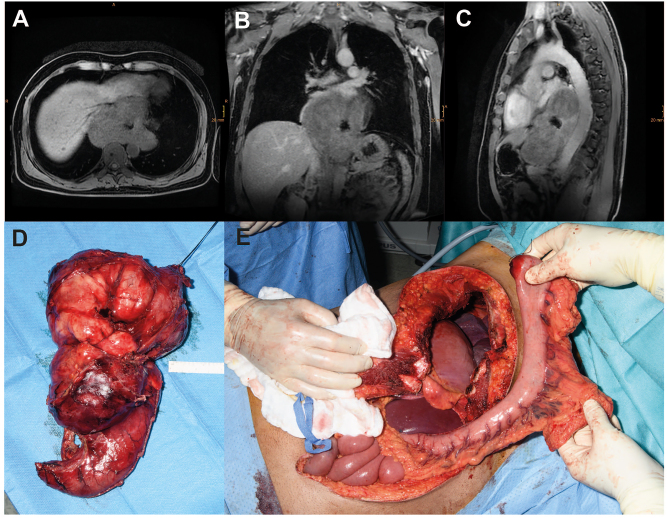

Abstract Image